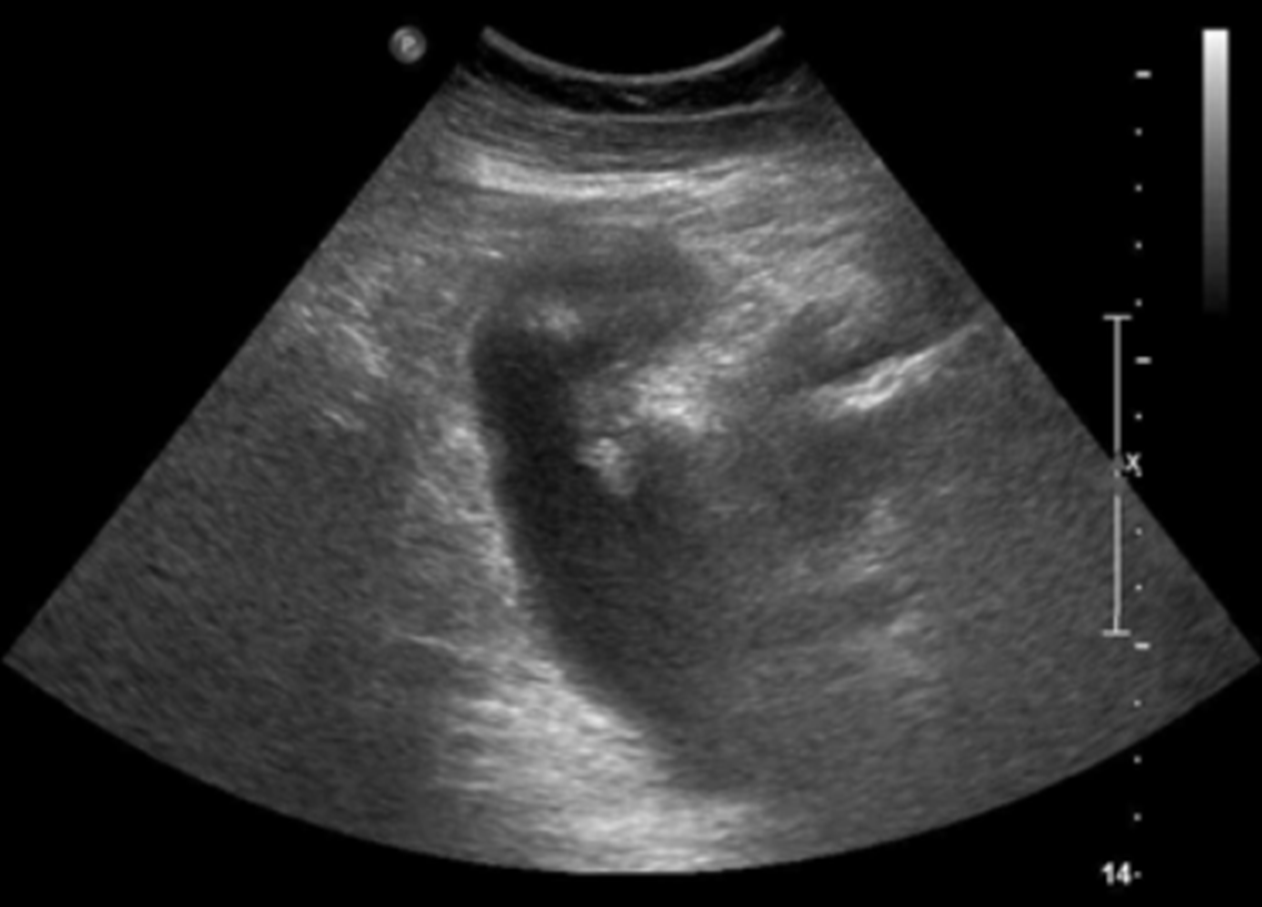

US: Gallbladder mass without posterior shadow

• 복부 초음파 검사에서 담낭벽에 후방음영이 없는 덩이가 관찰되었다. 해당 병변은 불규칙한 형태heterogenous한 내부 구조를 보이고, 비대칭적인 담낭벽 비후를 동반하였다. 또한 크기가 1cm 이상으로 관찰되어 담낭암 가능성을 강력하게 의심해야 한다